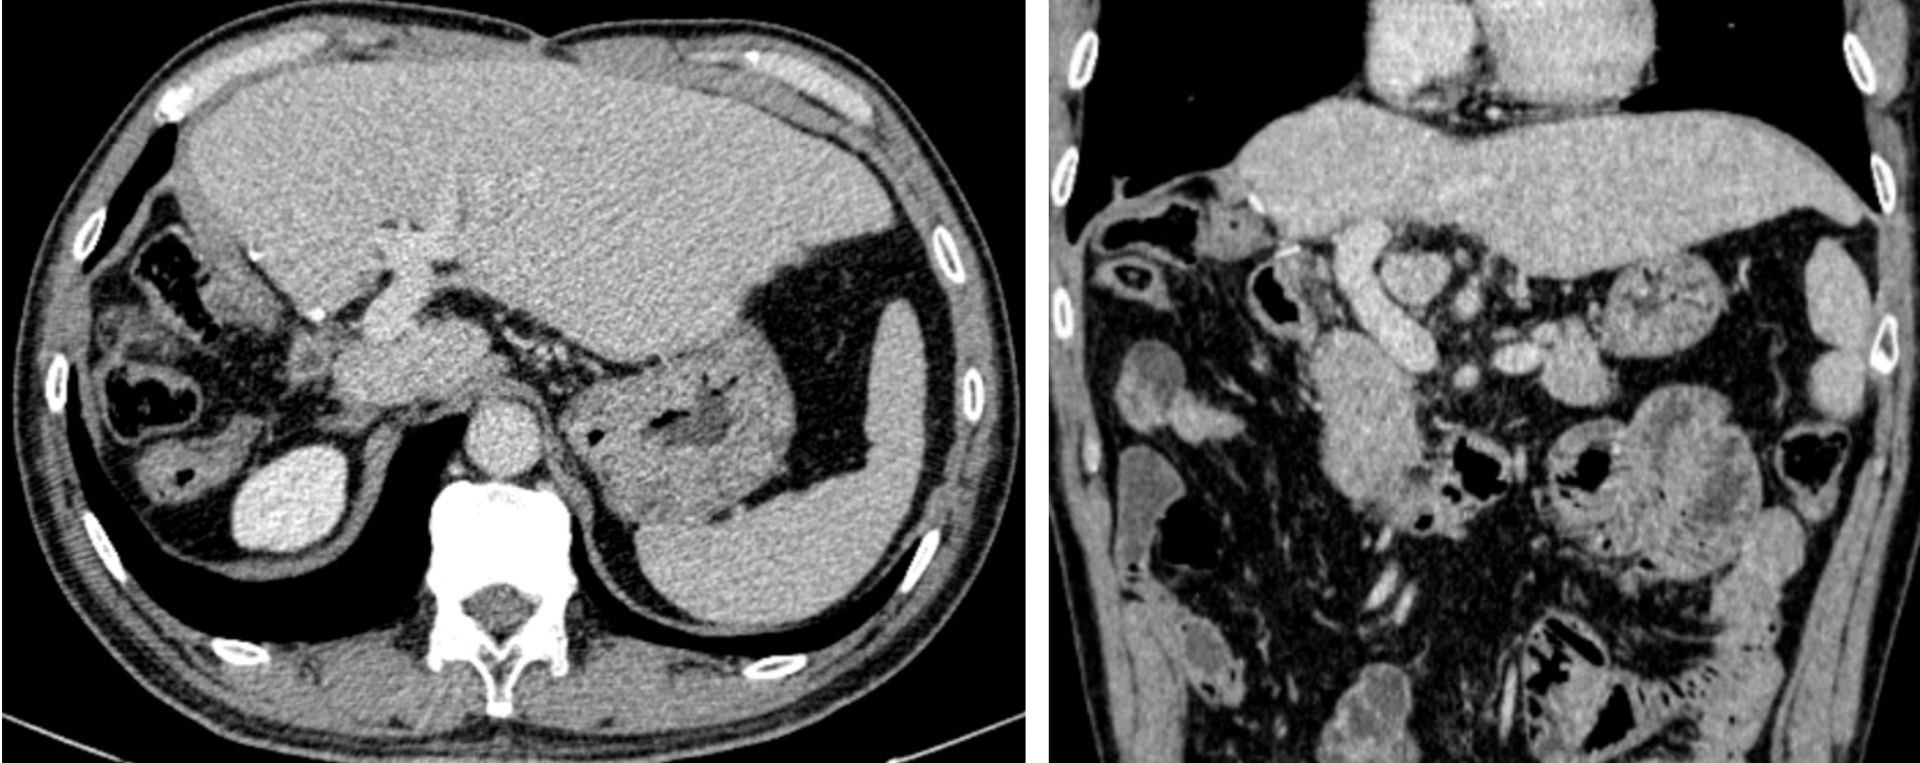

Sau 4 năm tái khám định kỳ, kết quả chụp cắt lớp vi tính cho thấy gan trái của bệnh nhân hoạt động tốt, tĩnh mạch cửa thông thoáng, không phát hiện u tái phát tại gan và không có di căn xa – một kết quả hiếm gặp đối với ung thư gan giai đoạn muộn kèm huyết khối tĩnh mạch cửa.

| Hình ảnh chụp cắt lớp vi tính sau 4 năm cho thấy gan trái tốt, không tái phát, không di căn xa. |